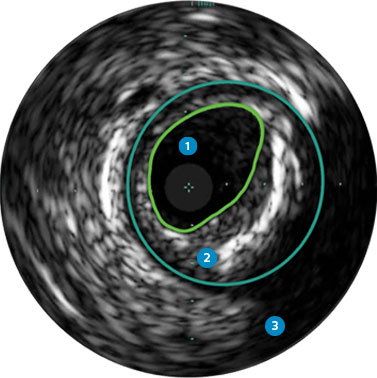

Behandlungsplan Beispiel 1

Lumen

Exzentrische fibröse Plaque mit tiefliegendem Calcium

Schallschatten

Gefäßgröße: 5,5 mm Durchmesser Plaquemorphologie: fibröse Plaque mit intimalem und mittlerem Calcium Plaquegeometrie: exzentrische Läsion Position des Führungsdrahtes: wahres Lumen

Quick-Cross-Katheter: souverän komplexe Morphologien durchqueren Direktionale Atherektomie mit Phoenix: frontal zum Schneiden, Erfassen und Freilegen gemischter Morphologien, einschließlich Kalzium; Möglichkeit der Richtungssteuerung für größeren Lumengewinn AngioSculpt Scoring-Ballonkatheter: Calcium messen, um eine Dissektion zu reduzieren4 Stellarex DCB: entwickelt für hohe Leistungsfähigkeit bei Kalzifizierungen